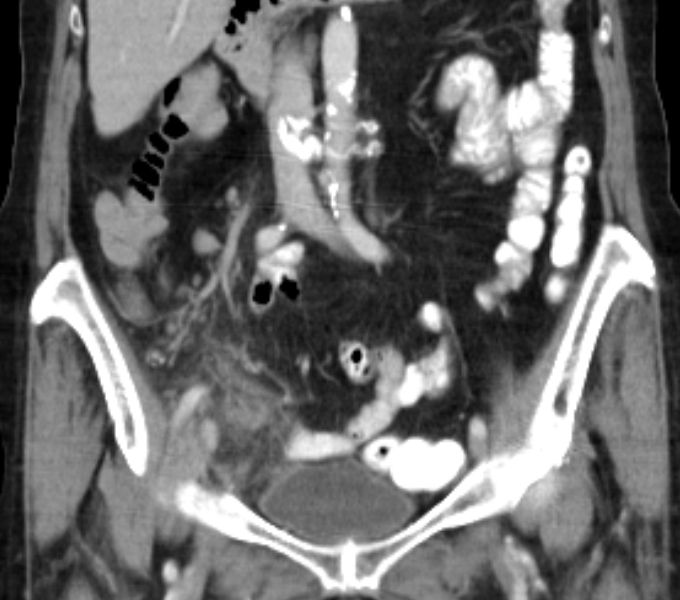

71-jährige Frau mit Adenokarzinom der Appendix pT4b pNo Mo Lo Vo.

Coloskopie: zirkuläres, exophytisch und ulzerierend wachsendes Karzinom mit einer Größe von 60 mm im Colon ascendens, nicht passierbar.![]() |

![]() |

Unmittelbar oberhalb der Ileozökalklappe Nachweis eines 7 x 6 cm großen, schüsselförmig exulzerierten Tumors.

Der Tumor durchdringt alle Wandschichten und infiltriert retrograd den davor geschalteten Dünndarm.![]() |